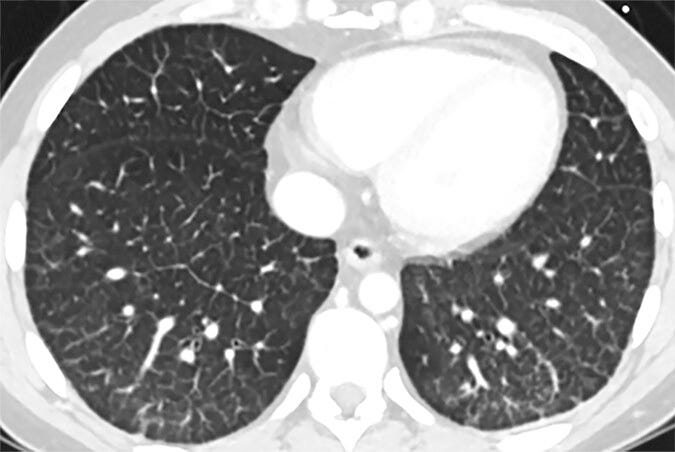

Something clicked for me reading Ricky’s Substack article “30 Clues That Let Us Know COVID Was A Planned Operation | Part VIII: EVALI” and I can’t stop thinking about it. He points out that the lung injury labeled as “COVID lung” looked almost identical to what doctors were already seeing in heavy vape users for years. Ground glass imaging. Scarred bronchioles. Oxygen exchange that never quite recovers. The clinical picture of bronchiolitis obliterans, more commonly called popcorn lung. The common factor is not some mythical viral enemy. The common factor is heat… plus nanoparticles.

Radiologists call the result “COVID lung” or “popcorn lung”. The mechanism has been staring us in the face for years. It’s. So. Simple. Call it what you want. Popcorn lung. Hair product lung. COVID lung. Nanoparticle lung. Not a virus making my long not work lung.